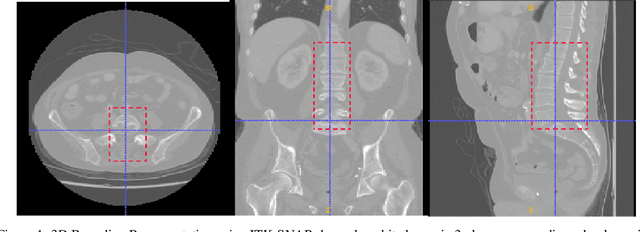

Abstract:Computer aided diagnostics often requires analysis of a region of interest (ROI) within a radiology scan, and the ROI may be an organ or a suborgan. Although deep learning algorithms have the ability to outperform other methods, they rely on the availability of a large amount of annotated data. Motivated by the need to address this limitation, an approach to localisation and detection of multiple organs based on supervised and semi-supervised learning is presented here. It draws upon previous work by the authors on localising the thoracic and lumbar spine region in CT images. The method generates six bounding boxes of organs of interest, which are then fused to a single bounding box. The results of experiments on localisation of the Spleen, Left and Right Kidneys in CT Images using supervised and semi supervised learning (SSL) demonstrate the ability to address data limitations with a much smaller data set and fewer annotations, compared to other state-of-the-art methods. The SSL performance was evaluated using three different mixes of labelled and unlabelled data (i.e.30:70,35:65,40:60) for each of lumbar spine, spleen left and right kidneys respectively. The results indicate that SSL provides a workable alternative especially in medical imaging where it is difficult to obtain annotated data.